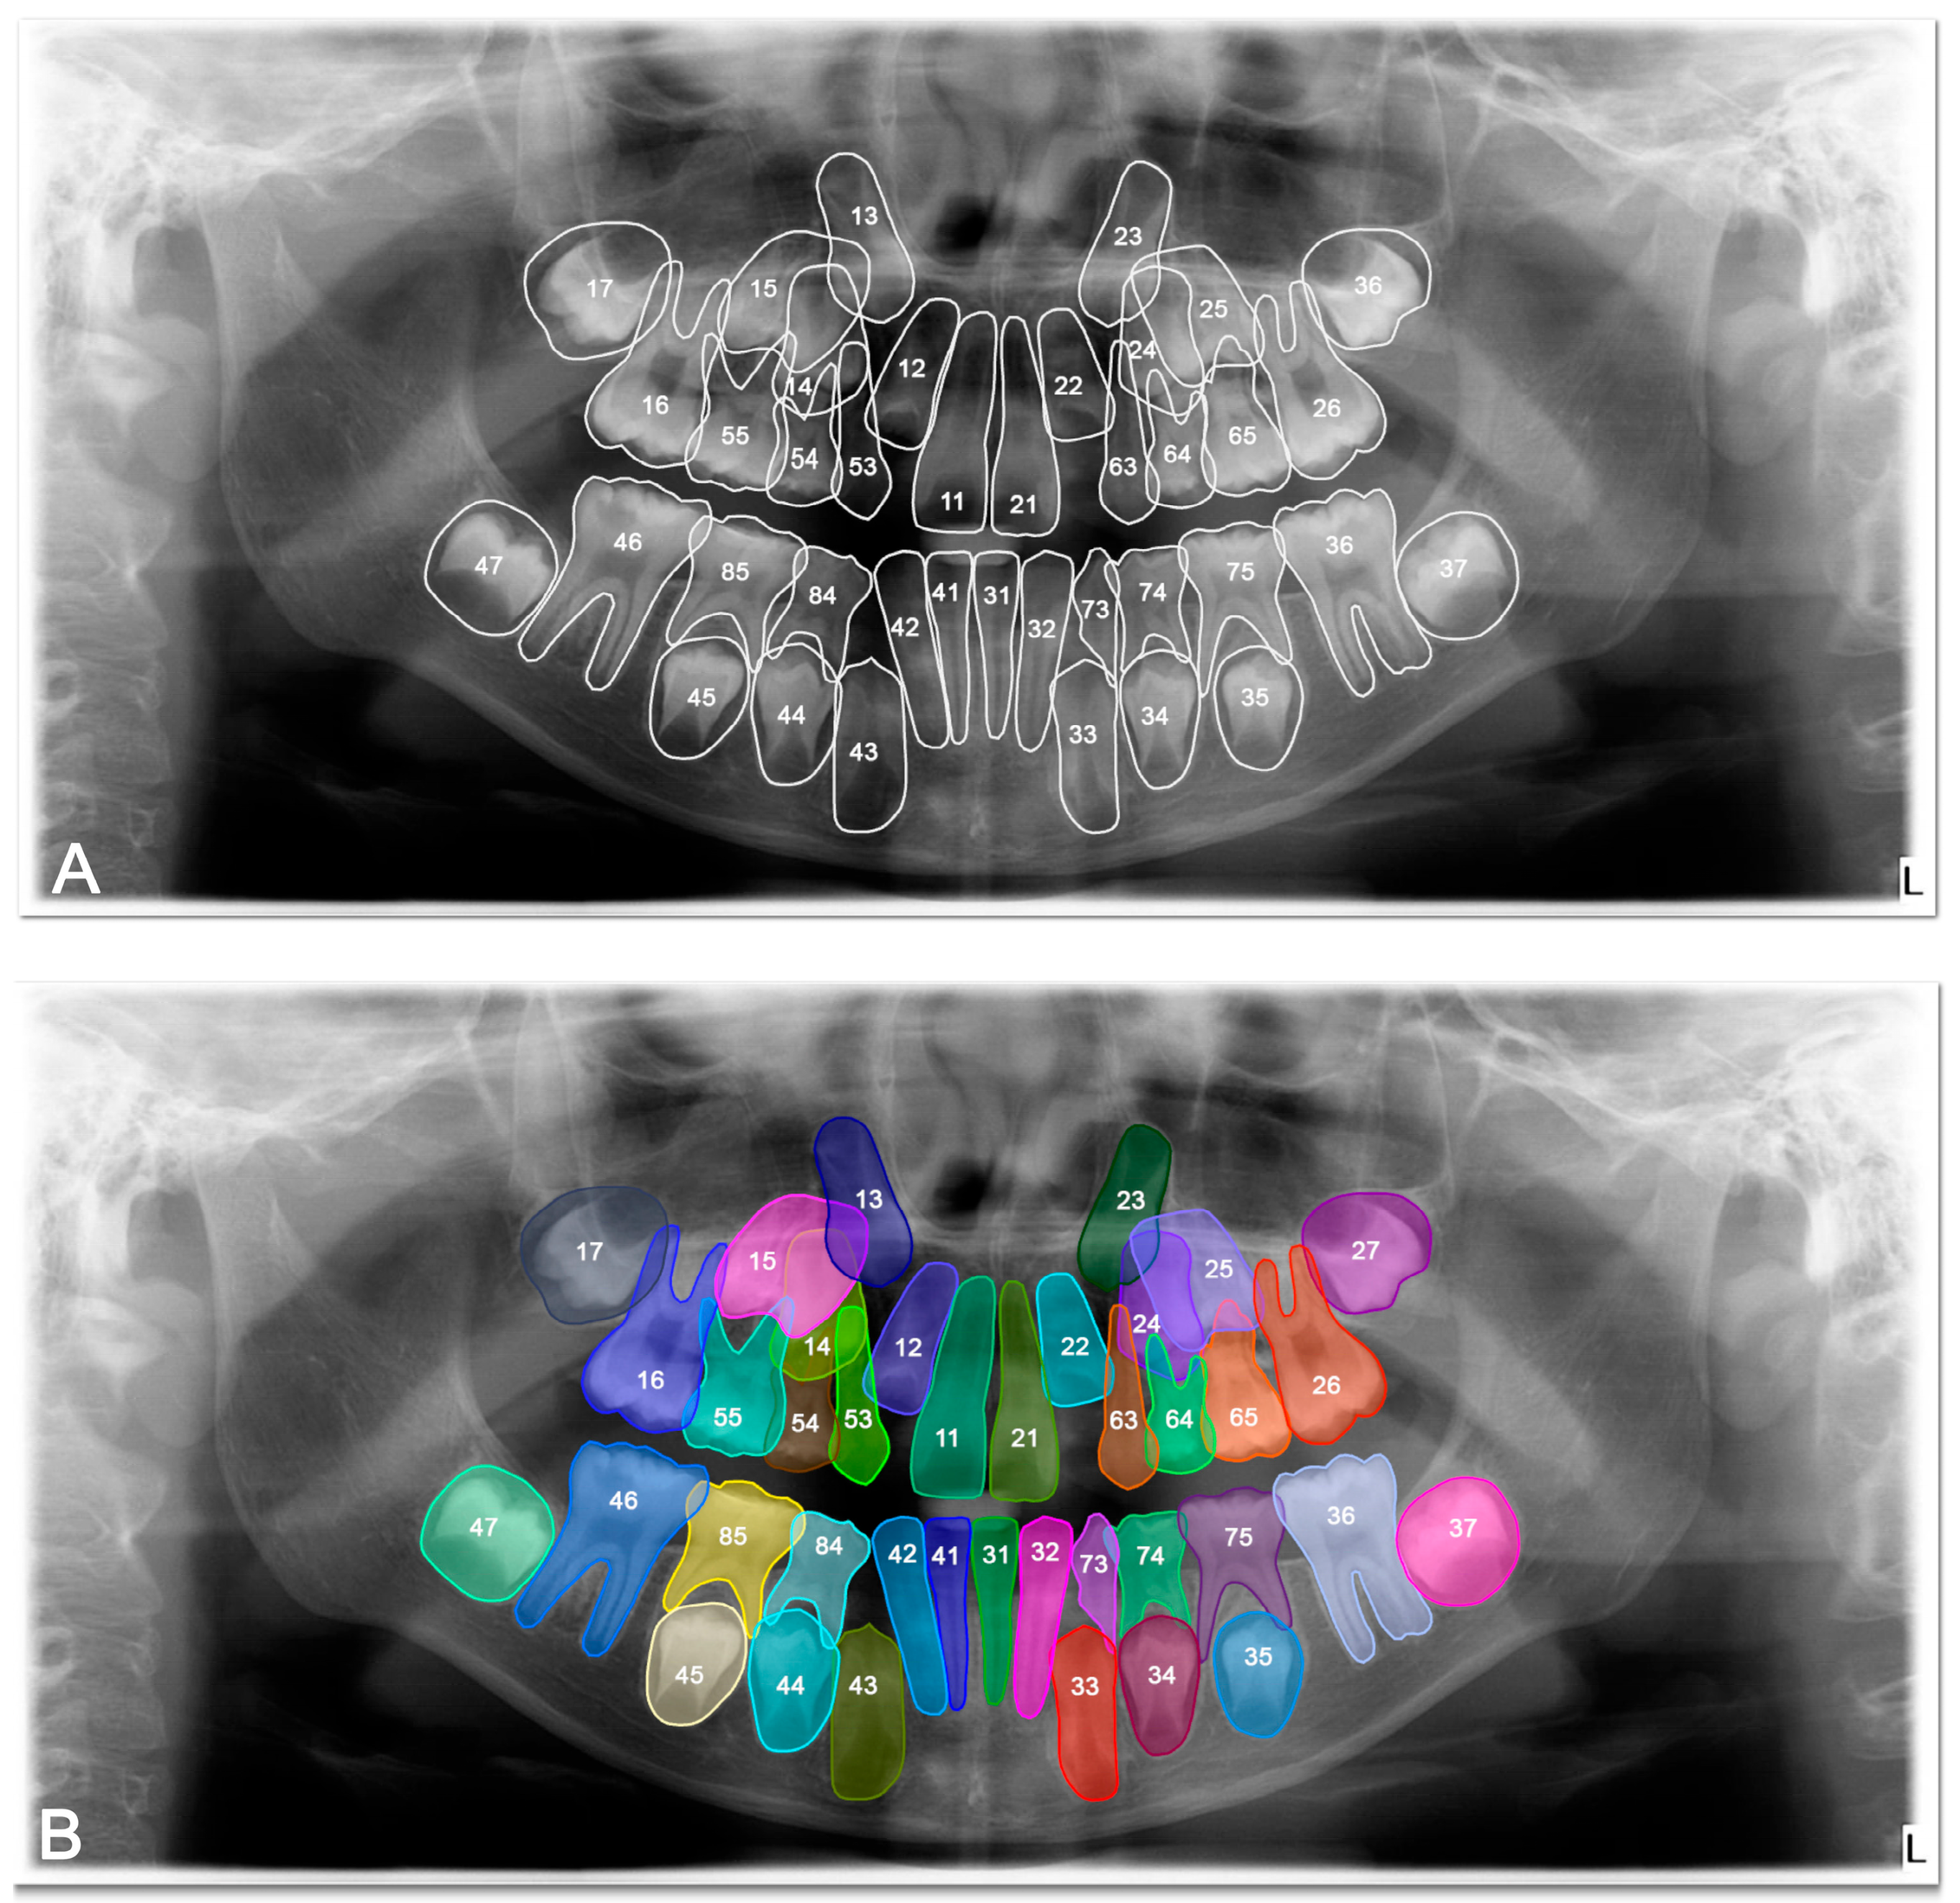

The DSC, precision, recall and F-1 score were 0.8692, 0.9078, 0.8925, and 0.9035 respectively, for tooth detection (Table 2). Examples for the detection of agenesis are shown in Figure 4.

Figure 4. Images demonstrating the performance for tooth agenesis detection on panoramic radiographs between manual annotation by three dentists and U-Net based artificial intelligence (AI)-predicted label masks. (A) Manual segmentation performed by clinicians. (B) Automatic segmentation by the model. In the segmentation figures, each tooth is represented with a distinct colour to visually differentiate regions; however, the model treated all teeth as unified segmentation classes during training.